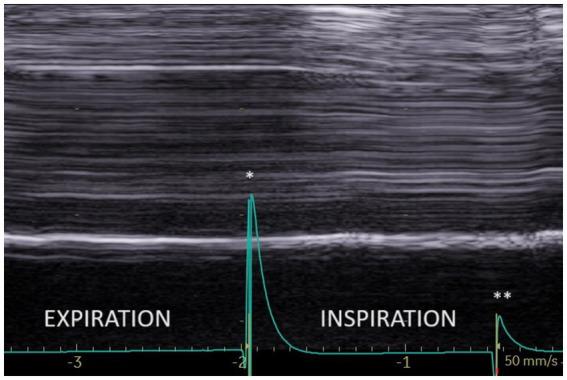

On paralyzed hemidiaphragm, thickening was less than 20% in all patients during deep inspiration. Thinning was recorded in 53% of cases. In some cases, the recording of the thickening could be difficult. The study of motion during voluntary sniffing reported a paradoxical excursion in all but one patient. During quiet breathing, an absence of movement or a paradoxical displacement was observed. During deep inspiration, a paradoxical motion at the beginning of inspiration followed by a reestablishment of movement in the cranio-caudal direction was seen in 82% of cases. In some patients, there was a lack of movement followed, after an average delay of 0.4 s, by a cranio-caudal excursion. Finally, in 4 patients no displacement was recorded. Evidence of hyperactivity (increased inspiratory thickening and excursion) of contralateral non-paralyzed hemidiaphragm was observed.